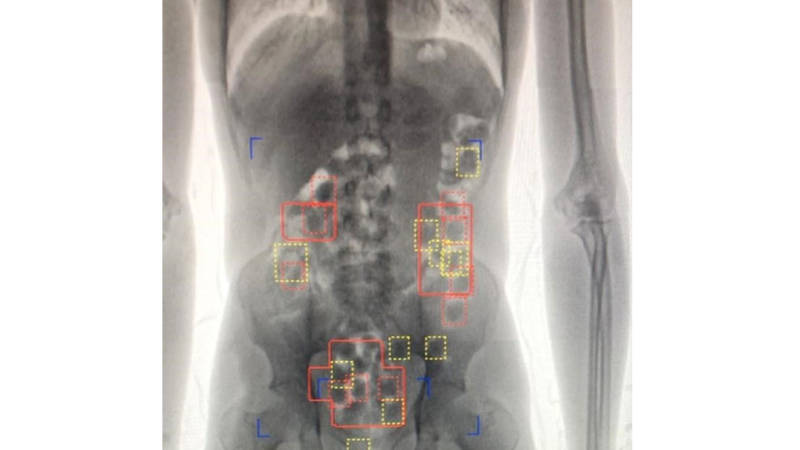

أثمرت جهود جمارك دبي في تطوير قطاع التفتيش الجمركي من صقل ضباط الجمارك عبر الدورات التدريبية المتخصصة والمبتكرة، وتزويد المراكز الجمركية بأحدث أجهزة الفحص عن كشف 16 محاولة تهريب مواد مخدرة عبر الأحشاء، بمطارات دبي خلال الشهور التسعة الأولى من العام الجاري، وتعد ضبطيات الأحشاء من أهم الضبطيات التي تعتمد على كفاءة وقدرة المفتش الجمركي في الكشف عنها، ومهنيته العالية في قراءه لغة جسد المسافر؛ حيث أسفرت هذه الضبطيات عن تحريز عدد 1457 كبسولة تحتوي مواد مخدرة بوزن 12285.6 جرام.

قال إبراهيم الكمالي مدير إدارة عمليات المسافرين في جمارك دبي: تعد جمارك دبي داعماً رئيسياً لريادة مطار دبي الدولي عالمياً؛ حيث ساهمت عمليات التحديث المستمرة لأجهزة الفحص الجمركي التي تقودها جمارك دبي على مستوى الدولة بشكل رئيسي في محافظة مطار دبي الدولي، على مركزه كأول مطار في العالم؛ من حيث إجمالي أعداد المسافرين الدوليين، فالتقنيات العالية التي تتمتع بها هذه الأجهزة تدعم تسريع وتيرة إجراءات عبور المسافرين ورسم الابتسامة على وجوههم من جهة، والكشف عن المواد الخطرة والمحظورة والمقيدة من جهة أخرى، مشيراً إلى أن أساليب التهريب تتنوع حسب نوع المادة المهربة وحجم الشحنة ووسيلة النقل؛ وذلك فيما يخص البضائع، وفيما يخص المسافرين يتوقف الأمر على طبيعة المادة المهربة؛ حيث يلجأ المسافرون لحيل متنوعة جديدة منها إخفاء المواد المخدرة في الملابس، وفي قاع الحقائب الكبيرة مع ابتكار جيوب سرية لها، والحقائب اليدوية، وفي الصناديق المغلفة، أو ابتلاعها على شكل كبسولات، وتعتمد كشف هذه الحيل على فرق التفتيش بالمطار ومهاراتهم في تحديد المهربين.

كشف فلاح السماك مدير أول مبنى 2 أن عدد ضبطيات الأحشاء التي أنجزت في مبنى المطار رقم 2 خلال الشهور التسعة الأولى من العام الجاري سجل 11 ضبطية بعدد 1051 كبسولة وبكمية 7560.99 جرام من المواد المخدرة، مؤكداً أن تكامل وحدات التفتيش من فرق الجوالة وغرفة العمليات والمفتشين في صالة القادمين والعمل بروح الفريق الواحد؛ أسهم في الإيقاع بالمهربين، وحماية المجتمع وأفراده من هذه الكمية من المخدرات.

وأوضح: إن من أبرز ضبطيات الأحشاء في مبنى 2 ضبطية لمسافر من الجنسية الآسيوية؛ حيث تم الاشتباه فيه من قبل موظف قسم التفتيش في «صالة القادمون»؛ بعد أن لاحظ المفتش على المسافر علامات التوتر والارتباك فتم تحويله إلى جهاز الكشف بالأحشاء وبعرضه على جهاز كشف تبين وجود أجسام غريبة في أحشائه وبسؤاله عما يحمله بأحشائه اعترف المسافر بأنه يحمل في أحشائه عدد (70) كبسولة ولا يعلم محتواها فتم تحويله على إدارة مكافحة المخدرات ليتبين أن عدد الكبسولات بلغ 82 كبسولة بوزن 927.75 جرام من مادة الهيروين المخدرة.